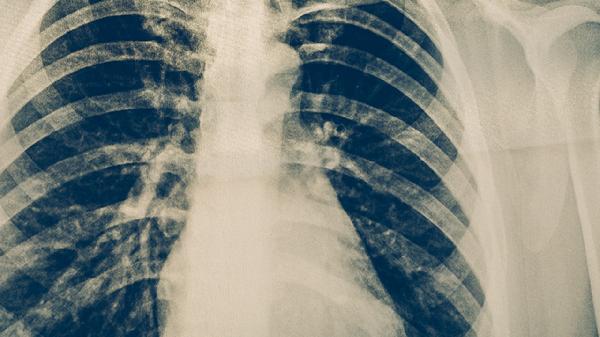

肺结核早期最常见的症状是咳嗽,通常持续2周以上。咳嗽初期可能为干咳,随着病情发展可能出现咳痰,痰液可能呈现白色黏液状或带有血丝。咳嗽在早晨或夜间可能加重,影响正常休息。肺结核引起的咳嗽与普通呼吸道感染不同,常规止咳药物效果有限。若咳嗽持续不缓解,建议及时就医进行胸部影像学检查和痰液结核菌检测。

肺结核早期症状缺乏特异性,容易与其他呼吸道疾病混淆。若出现上述症状持续2周以上,建议及时到呼吸内科或感染科就诊。确诊肺结核后应严格遵医嘱进行规范抗结核治疗,常用药物包括异烟肼片、利福平胶囊、吡嗪酰胺片、乙胺丁醇片和链霉素注射液等。治疗期间应注意休息,保持室内通风,避免传染他人。饮食上应保证充足热量和优质蛋白摄入,适当补充维生素和矿物质。定期复查胸部影像学和肝功能,监测治疗效果和药物不良反应。完成全程治疗是治愈结核病的关键,不可擅自停药或减量。